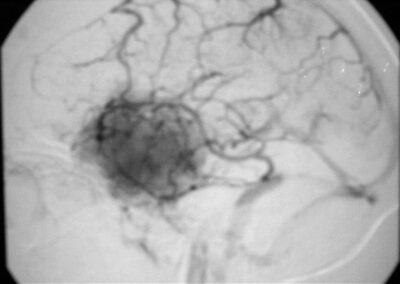

El diagnóstico se puede confirmar y el tumor localizar mediante:

• Angiografía cerebral